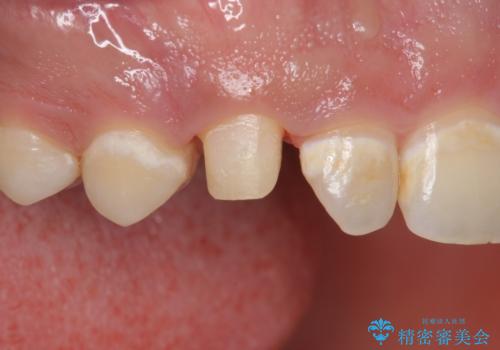

- 「前歯に穴が開いたから診てほしい」とのことで来院。

全体的に歯と歯茎の間境目が白く、右上の前歯は穴が開いてしまっていました。

インレーでの修復はできない場所であるため、セラミッククラウンでの治療になりました。

全体的に歯の脱灰が目立っており、右上の犬歯のみ状態が悪く穴が開いてしまっていました。